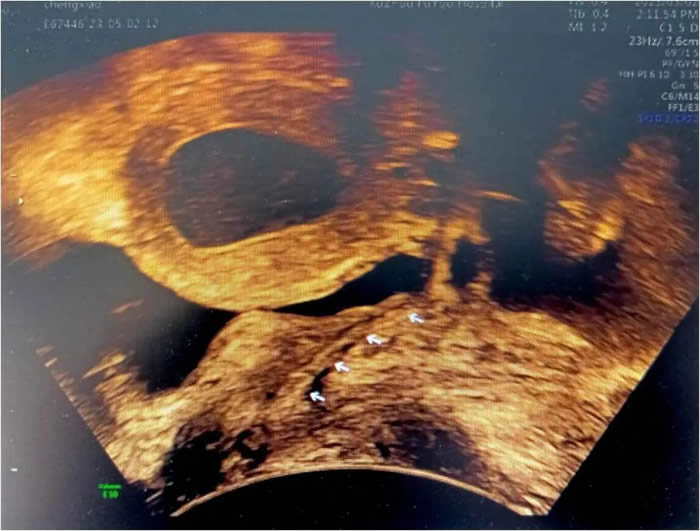

小玲(化名)13歲(suì),到徐州市婦(fù)幼保健院就診時,周期性腹痛已持續一年之久,不僅影響了孩子的學業、整個家(jiā)庭也陷入了無限的困境。經各項檢查發現,小玲患有先天梗阻性生殖道發育異常,先天性無陰道和條索狀宮頸。雖然如此,小玲的(de)子宮卻發育良好,所以每次月經來潮時,經血無法正常排出,隻能通過輸卵管逆流到盆腔,導致難以忍(rěn)受的腹痛。小玲也曾在(zài)父母的陪(péi)同(tóng)下(xià)到(dào)國內多家大醫院就診,給出的治療(liáo)方案均是切除子宮(gōng)體,等待時機做二期陰道成(chéng)形(xíng)手(shǒu)術,這對於一個13歲的女孩,還有父母來說是難以接受的。

早在進行前期檢查時,李(lǐ)教授就發現小玲一側輸卵管因經血逆流造成嚴重積水傘端封閉,已失去了(le)保留價值。如果能將積水的輸卵管休整(zhěng)後移植到(dào)子宮下端(duān)代替宮頸管(guǎn),便能變廢為寶。但國內、外關於(yú)先天性陰道、宮頸發育異(yì)常的Ⅱ型(xíng)陰道閉鎖保留子宮的手術(shù)成功(gōng)案例十(shí)分罕見,可參(cān)考的資料更是少之又少。國內、外文獻檢索(suǒ)亦未見有使(shǐ)用輸卵管代替宮頸管的案例報道(dào),也是李桂林教授團(tuán)隊在醫學未知領域的又一次“創新之旅”。